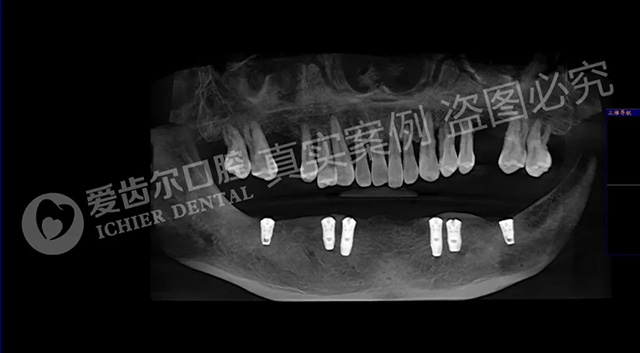

种植前拍片检查,下颌牙龈萎缩严重↑

下颌植入6颗植体↑

种植修复后效果↑